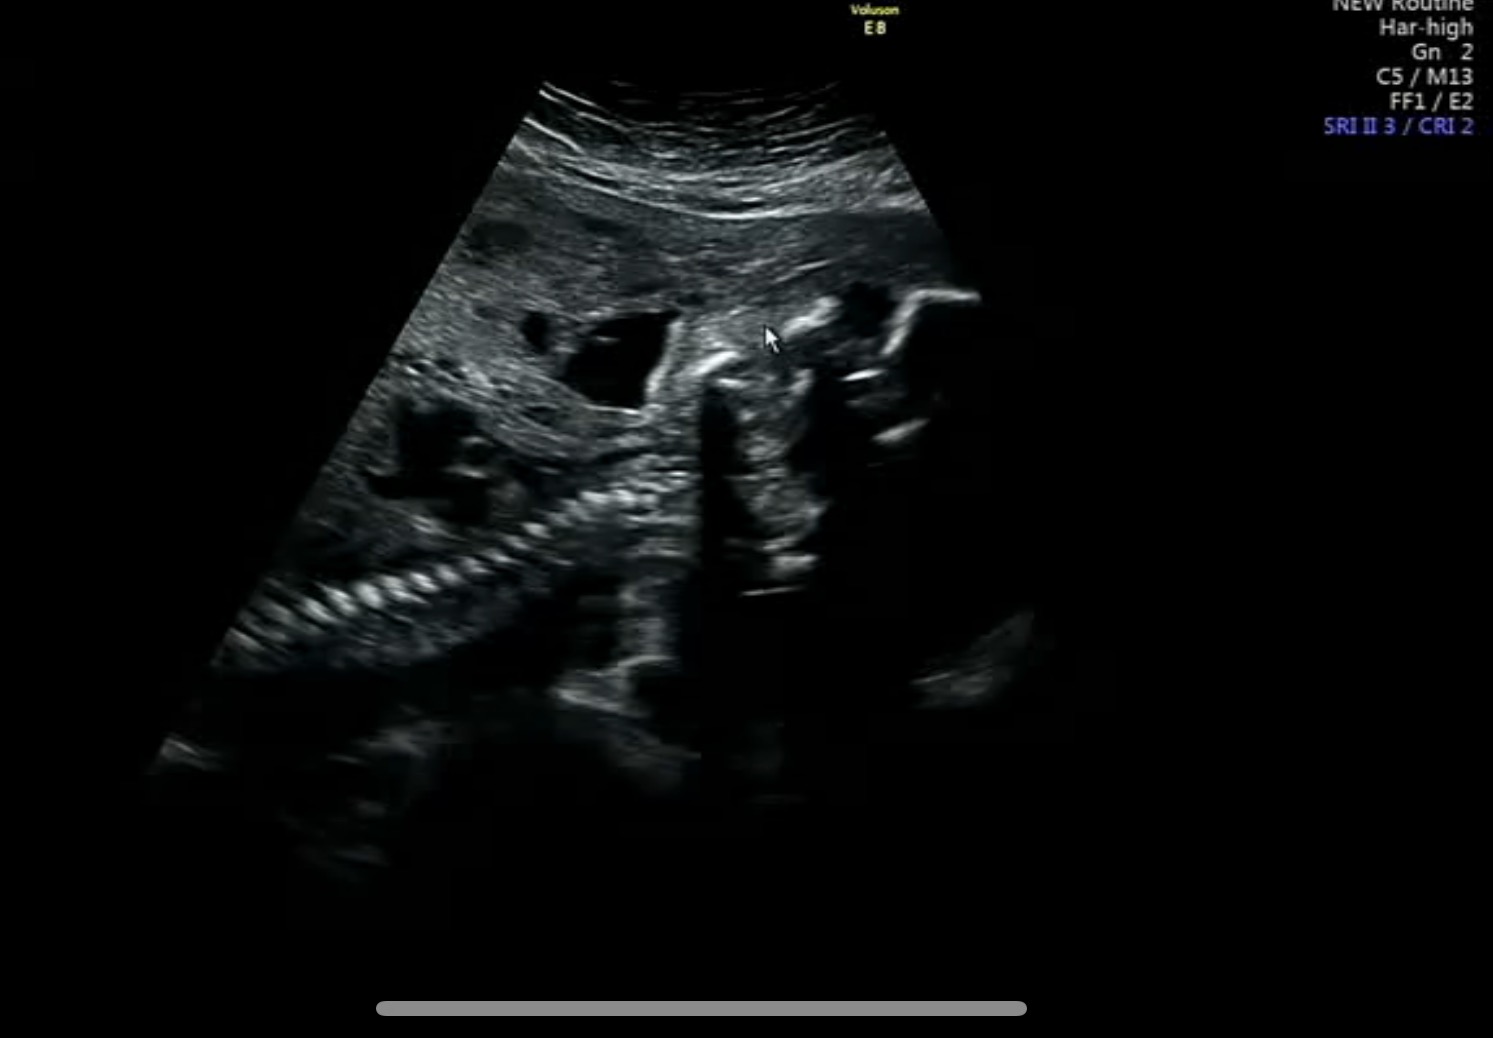

얼굴은 보여주기 싫은지 자궁벽에 콕 처박고 있었다.

심장으로 들락날락하는 혈관도 괜찮다고 하고

신장, 위, 간, 척추 등도 괜찮다고 했다.

엽산대사이상 CT형이라 척추 모양을 유심히 봤는데,

끊긴 곳이나 틀어진 곳이 내 눈에 딱히 띄지 않아서 더 질문하진 않았다.

탯줄에 보이는 혈관도 3줄로 정상으로 보인다고..

크기가 좀 작긴하지만 문제될 정도는 아니라고 했다.